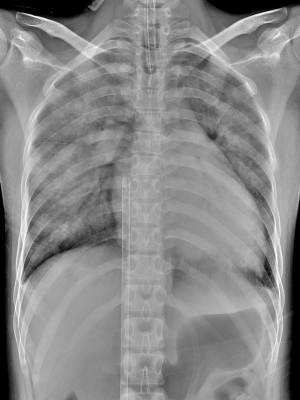

十八歲鄭小姐因周產期心肌病變導致心臟衰竭和肺水腫,在治療期間突發心律不整,二度心臟驟停,雖然急救後恢復心跳,但心臟各項數值表現仍相當不樂觀,花蓮慈濟醫院心臟內外科團隊運用葉克膜和心室輔助器爭取時間,維持心肺功能的正常,並持續悉心照護,鄭小姐的病況很快恢復穩定,在急救後十天移除心室輔助器,二十一天後出院返家,目前心臟功能幾乎已回到生病前的狀態,重返育兒新生活。

圖:鄭小姐裝上葉克膜六小時後,胸腔X光影像中肺部幾乎呈白色,肺水腫嚴重且心臟明顯擴大。

圖:鄭小姐出院後第二次回診檢查,胸部X光影像顯示肺部與心臟已恢復正常。